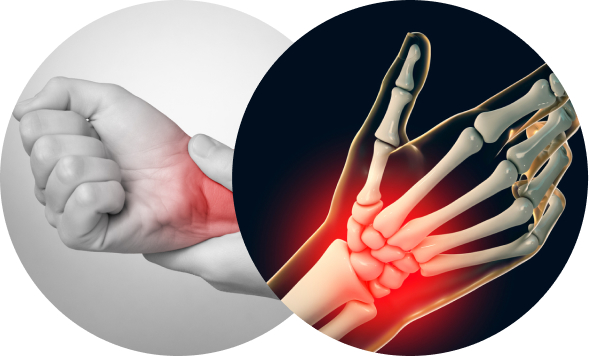

반복된 손목 사용으로 인해 염증이 발생하는 것입니다.

스마트폰, 컴퓨터 사용이 늘면서 손목터널증후군을 앓는 환자가 늘고 있습니다.